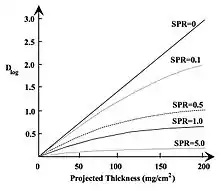

- A third theoretical advantage of logarithmic subtraction is the generation of images in which the image density is directly proportional to the projected thickness of the contrast medium, ρctc. This feature has given rise to the use of densitometric analysis of images so as to derive clinically-useful indices of function, e.g. percent stenosis and left ventricular ejection fraction. However, it is important to note that the above reasoning is based on a number of simplifying assumptions (e.g. monoenergetic radiation, no scatter) which when included in the treatment above invalidate the general conclusions reached - see Figure 7.3. Nevertheless, logarithmic subtraction is widely applied in clinical DSA.

- Figure 7.3 illustrates the dependence of Dlog on the projected thickness of contrast medium for a range of scatter-to-primary ratios (SPRs), i.e. the ratios of the intensities of detected scattered and primary radiation. These plots were generated by including scatter contributions in the above analysis. It is seen in the figure that Dlog is reduced significantly as the SPR increases and that the dependence on projected thickness becomes non-linear. For example, it is seen that Dlog is reduced, at a projected thickness of 50 mg cm-2, by about 85% when the SPR=5 relative to the no scatter condition, i.e. the contrast of an opacified blood vessel will be reduced by this factor. In addition, it is seen that Dlog becomes relatively independent of projected thickness, above about 20 mg cm-2 when SPR=5, for example, so that the ability to discriminate different projected thicknesses, and hence vessel opacity, is significantly impaired.

- A question relevant to this discussion relates to the SPRs that are typical of clinical imaging conditions. The following table shows measured SPRs for chest radiography to illustrate the situation. It is seen, for example, that the SPR is greater than unity for all anatomical regions when no grid is employed, i.e. the scatter intensity consistently exceeds the primary intensity. It is also seen that the greatest SPR reduction is achieved when a 12:1 grid is used. Referring now to the Figure 7.3, it can be seen that scatter reduction techniques, such as the use of an air gap or a grid are therefore likely to improve the contrast of opacified vessels and that their contrast will still be substantially reduced relative to the no scatter condition.